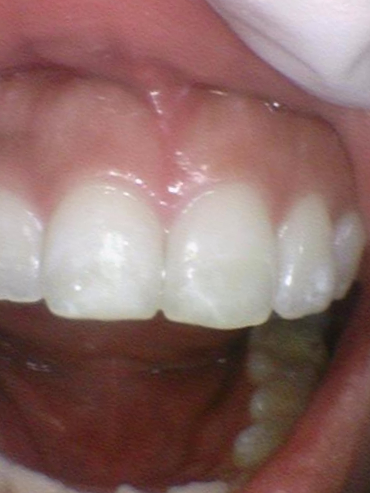

화이트스팟 치료 전후

위의 환자분은 화이트스팟 치료를 원하셔서 진행하였고

내원 30분 정도만에 화이트스팟을 잘 치료하셔서 일주일 후에 오셨을 때 만족한다고 말씀하셨습니다.